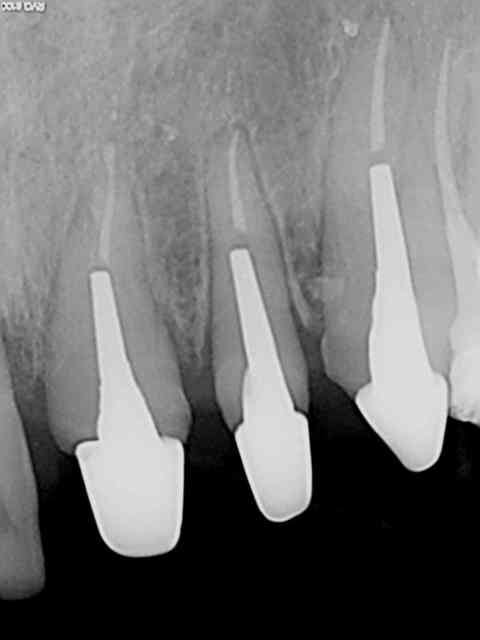

R1 jf6pzt - Eugenol

R2 k7cybs - Eugenol

R3 i3jjn6 - Eugenol

R4 dveqiy - Eugenol

Zoom incisives eb4rim - Eugenol

Retraitement et cour prov ej8sen - Eugenol

Canaux calcifi s e685ou - Eugenol

Avec provisoires o4ho8c - Eugenol

Lol ! je vois qu'on a la meme technique. c'est pas du no post no crown, mais je sais faire ca aussi. ))))))

Sur les monoradiculées, les tenons sont un peu trop courts. Avec les années, si l'os alvéolaire diminue, les risques de fractures de racines augmentent lorsque le bout du tenon se retrouve au niveau du rebord alvéolaire.

je fait extrêmement peu de tenon, mais tu nous présentes un travail soigné au moins d'un point de vue radiologique, sur la technique endo intrinsèque je laisse le soin a chacun de se faire une opinion